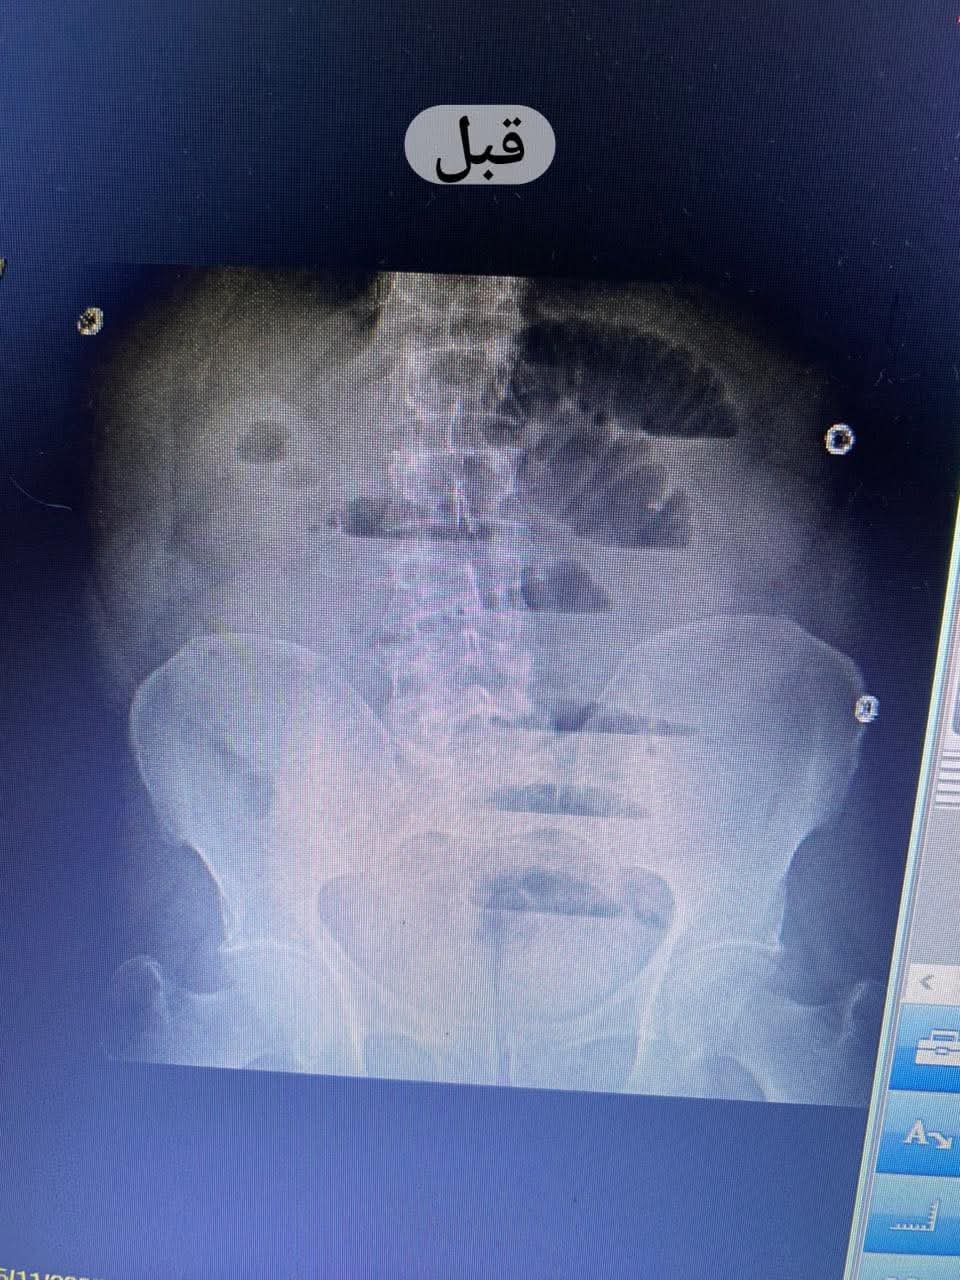

تم إجراء الفحوصات اللازمة حيث أظهرت الأشعة التليفزيونية والعادية على البطن وجود انسداد معوي كامل ناتج عن اختناق الأمعاء داخل كيس الفتق؛ ما استدعى سرعة تجهيز المريض لغرفة العمليات وإجراء عملية استكشاف للبطن على وجه السرعة وفقا للبروتوكولات العلاجية المعتمدة.